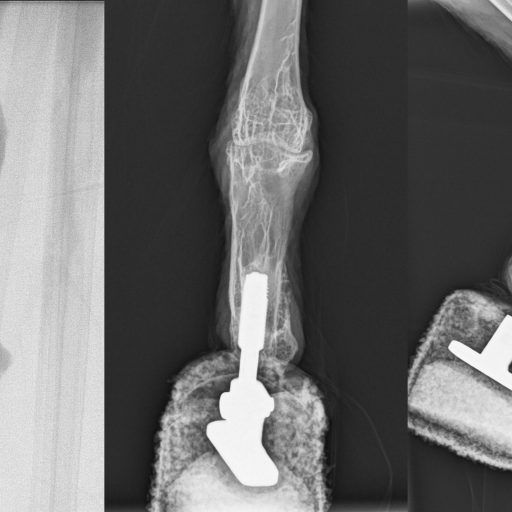

Diese neue Technik heißt Osseointegration und wurde von der Arbeitsgruppe Aszmann vor kurzem erstmals in Österreich bei einem Patienten nach Armverlust angewendet – bei einem Vogel war das zuvor noch nie gewagt worden. Bei der Osseointegration werden externe Prothesenteile direkt mit einem Knochenanker verbunden, um eine solide Skelettbefestigung zu gewährleisten. Aszmann: „Dieses Konzept bietet ein hohes Maß an Verkörperung, da die Osseoperzeption ein direktes intuitives Feedback liefert, das eine natürliche Verwendung der Extremität beim Gehen und Füttern ermöglicht. Nun ist uns erstmals eine derartige bionische Rekonstruktion einer Extremität eines Geiers gelungen.“

Die Operation bei dem Bartgeier wurde gemeinsam mit Rickard Branemark vom Center for Osseointegration Research (San Francisco) am Zentrum für Biomedizinische Forschung an der MedUni Wien (Leiter: Bruno Podesser) erfolgreich durchgeführt. Die Rehabilitation und prothetische Versorgung erfolgte wieder in Haringsee. „Schon nach drei Wochen erfolgten die ersten Gehversuche und nach sechs Wochen die vollständige Belastung. Heute kann der Bartgeier wieder mit zwei Füßen und als erster ‚bionischer Vogel‘ landen und gehen“, sagt Aszmann, der vor allem durch seine bahnbrechenden Arbeiten zu bionischen Händen weltweite Bekanntheit erlangte. Insbesondere der Fall von Patrick Mayrhofer sorgte 2011 auch in internationalen Medien für großes Aufsehen: Der junge Elektriker war 2008 beim Arbeiten in den Stromkreis geraten und hatte schwerste Verletzungen vor allem an der linken Hand erlitt, die funktionslos blieb. Er entschied sich daraufhin, sich die Hand amputieren zu lassen und – weltweit erstmalig – einige Wochen später durch eine bionische Prothese an der MedUni Wien ersetzen zu lassen.